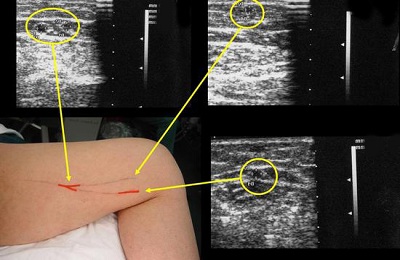

УЗИ вен и артерий выполняется точно так же, как и любой другое УЗИ.

Пациент занимает нужное положение на кушетке (оно будет зависеть от того, какие сосуды нужно визуализировать).

- На кожу исследуемой области наносят специальный гель, облегчающий процедуру визуализации.

- Врач прикладывает датчик к определенным точкам исследуемой области и получает картинку в режиме реального времени на экране УЗИ-аппарата.

Если есть необходимость исследовать глубокие сосуды, врач может просить пациента делать вдохи и выдохи, несколько изменять положение тела в ходе процедуры.